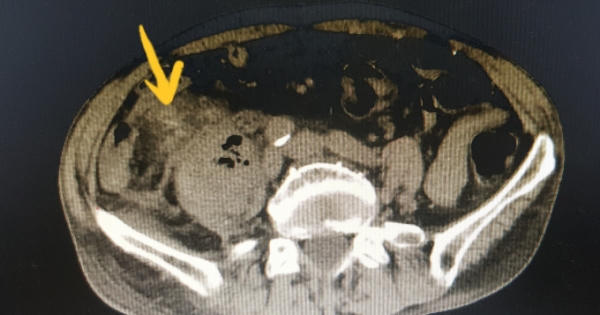

Hình ảnh chụp cắt lớp ổ bụng cho thấy, chiếc tăm xỉa rang dài 5 cm đã đâm thủng ruột cụ ông.